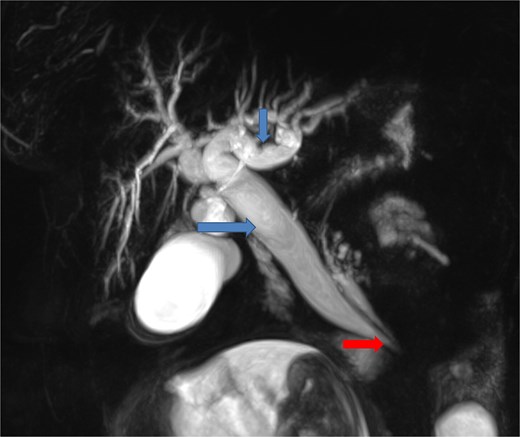

To better assess the biliary anatomy and clarify the cause of obstruction, a MR cholangiopancreatography (MRCP) was performed 2 days later. It confirmed the duodenojejunal invagination and demonstrated the involvement of the terminal bile duct within the intussuscepted segment (Fig. 4). An ectopic biliopancreatic confluence was also identified, draining into the fourth portion of the duodenum, likely predisposing the bile duct to traction and resulting in upstream dilation (Fig. 5).

Axial (a, b) and coronal (c) T2-weighted TrueFISP MR images confirming the duodenojejunal intussusception (white arrows) and showing inclusion of the terminal bile duct within the intussuscepted segment (red arrow), resulting in significant upstream biliary dilatation (blue arrow).